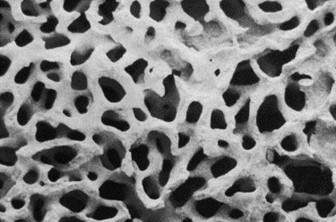

上述三種材料幾乎是同時在1980年代有人使用,但最先進入臨床試驗而被美國食品藥物衛生管理局核准上市者為 Coralline hydroxyapatite(俗稱珊瑚球)。珊瑚本為多孔隙物質,孔徑大小為300-700微米(um),顯微鏡下外觀如下圖

根據美國ASOPRS(American society of ophthalmic plastic and reconstructive surgeons)統計,在2000年以前最常用的義眼球為珊瑚材質,約有占一半的比例,但在2000年以後比例下降至25%。天然珊瑚做成的義眼球(商品名Bio-Eye)成本貴,而且破壞生態,之後有人工合成的珊瑚球(商品名 FCI3),優點是成本下降,而且相對於天然的珊瑚球,容易做義眼球鑽孔,裝上活動凹栓的義眼片後,義眼活動性更好。